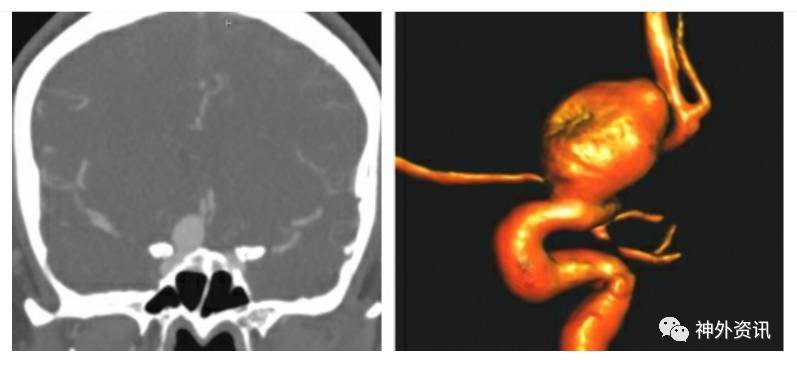

图1. 一例已确诊的右侧巨大眼动脉瘤,可见前床突(左)和眼动脉发出处(右)的关系很紧密。

CTA对于判断动脉瘤与骨性标记如前床突的关系上非常有帮助。而且它可以有效地评估动脉瘤在硬膜内的程度和是否需要治疗。